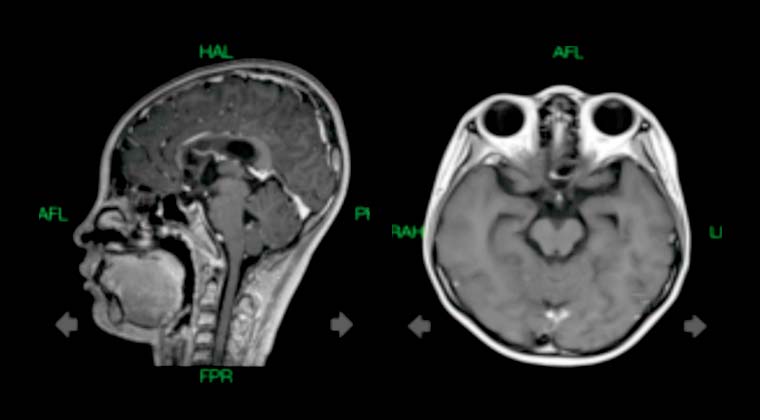

① Случай 1:

Пациентка: Девочка-подросток, 16 лет

Диагноз: Злокачественная опухоль мозга (внутричерепная герминогенная опухоль, IV стадия по классификации ВОЗ)

Симптомы: Периодическое головокружение, сухость во рту, жажда, полиурия

19.02022 - проведена радиотерапия TOMO

Дозы облучения: PTV 45 Гр / 1,8 Гр за сеанс / 25 сеансов

Контрольная визуализация через 10 месяцев показала значительное уменьшение опухолевых очагов в супраселлярной и шишковидной областях по сравнению с предыдущими исследованиями

До лечения:

После лечения: